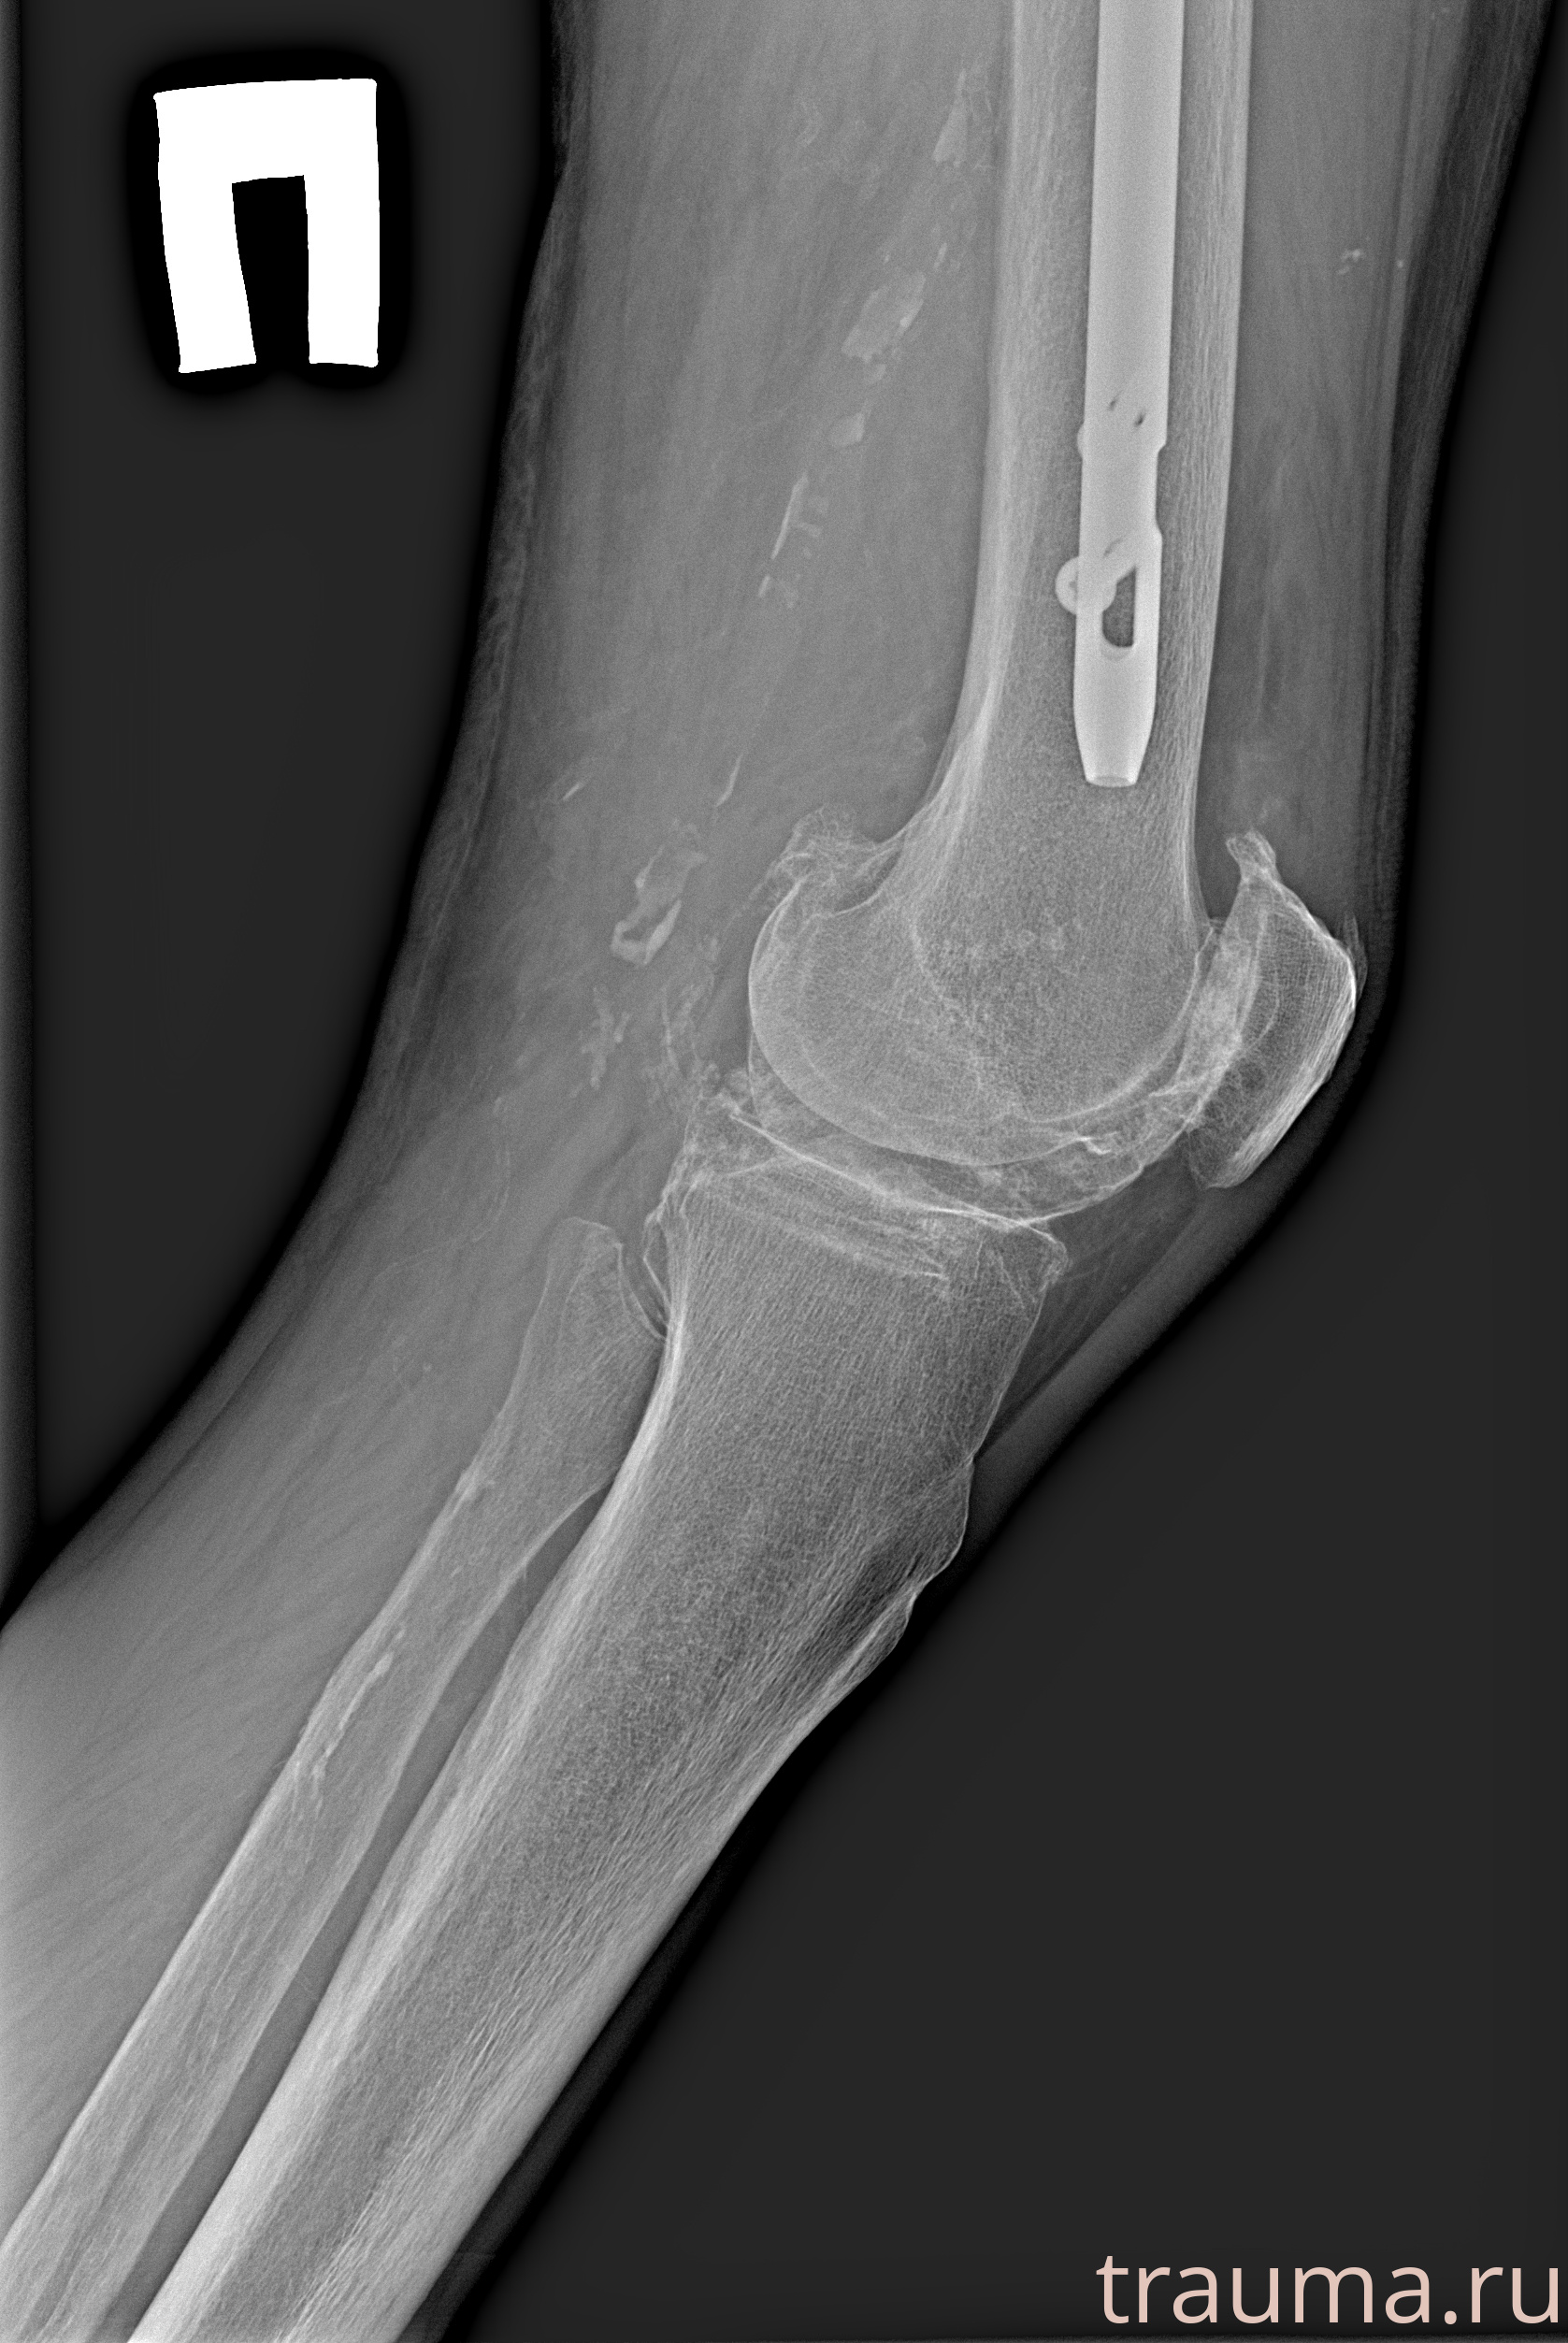

Рентген на дому: по вашему адресу приезжает врач-рентгенолог, травматолог-ортопед с мобильным рентгеновским аппаратом, проводит диагностику травмы или заболевания, делает необходимые рентгенограммы, дает рекомендации по дальнейшему лечению. Получить качественные снимки в домашних условиях возможно благодаря уникальной методике, разработанной МосРентген Центром для института  Склифосовского